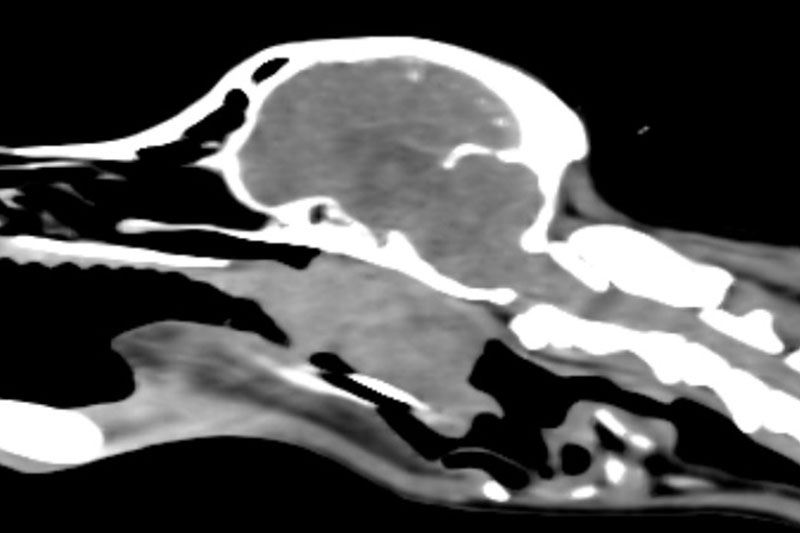

| 두부(머리) | 뇌종양, 두개골 골절, 중이염, 치주염, 안와(눈) 질환 등 |